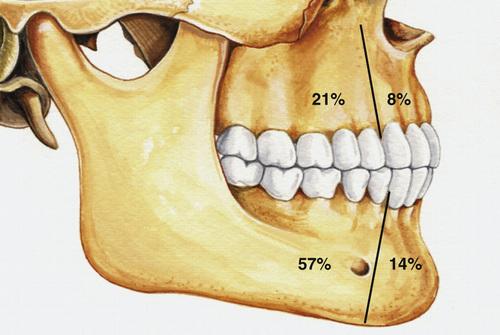

- most often occurs in the mandible (60% to 80%)

Radiographic Features

- well-defined radiolucent area

- large lesions may appear multilocular

- smooth and often corticated margins

- growth in an anteroposterior direction

- may involve an unerupted tooth (25% to 40%)